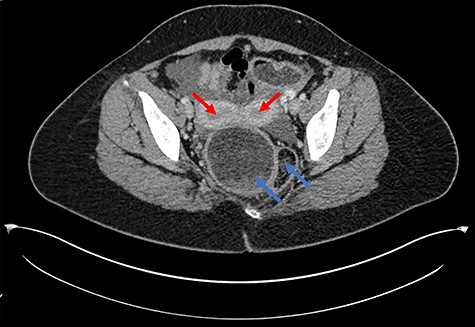

Axial CT scan demonstrating uterine didelphys (red arrows) and duplicated rectum (blue arrows).